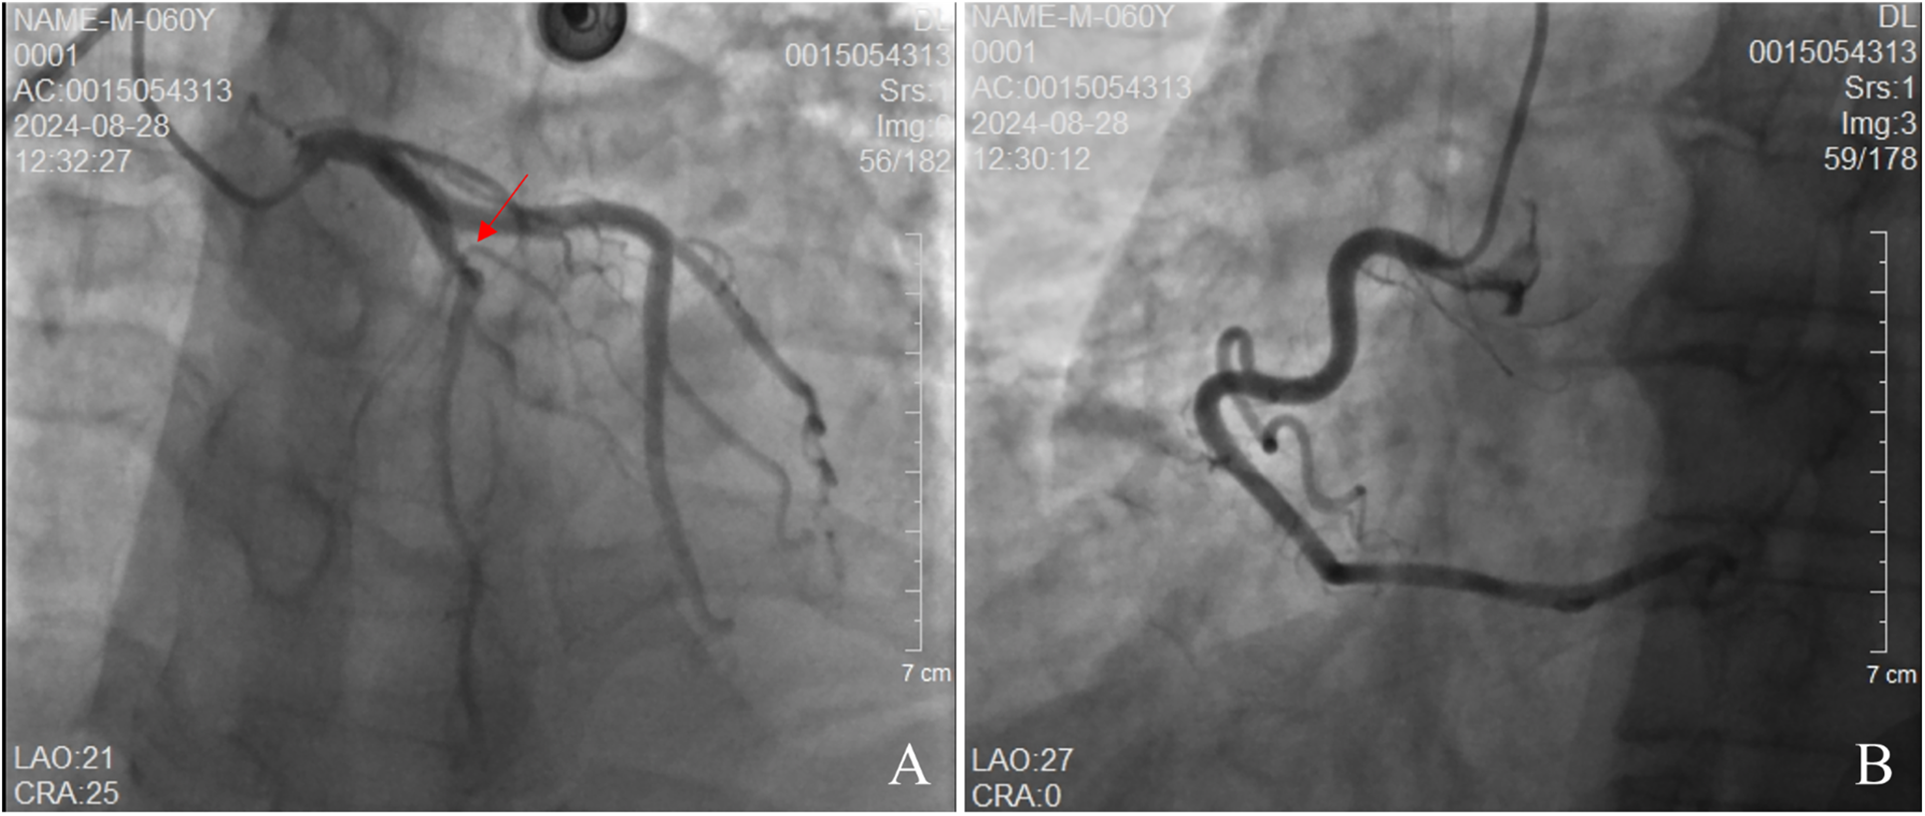

The patient's electrocardiogram was perfected on August 28, 2024 (see Figure 3), and compared with the ECG from July 15, 2024 (see Figure 4), changes in ST-segment elevation were observed in leads I, II, aVL, aVF, and V2–V5. Combined with the patient's symptoms, signs, elevated ultrasensitive troponin, and other indicators, an acute myocardial infarction was diagnosed. A coronary angiography was performed on August 28, 2024. No stenosis was seen in the left main stem (LM), the proximal stenosis in the left anterior descending branch (LAD) was about 60%, and no significant stenosis was seen in the left circumflex branch (LCX) or the right coronary artery (RCA). Coronary angiography results (see Figure 5). Combined with the results of coronary angiography, the diagnosis of acute myocardial infarction could be excluded. Medically, symptomatic treatments such as antiplatelet aggregation and lipid-lowering were given. During hospitalization, a cardiac ultrasound revealed a small amount of pericardial effusion (5 mm at the posterior left ventricular wall and 7 mm at the lateral wall) and limited abnormal echogenicity in the posterior lateral aspect of the left atrium. This area measured approximately 40 by 35 mm, was slightly hypoechoic, and the nature of the echogenicity was undetermined. Metastasis was not excluded based on the patient's history (see Figure 6). The patient continued with the ninth cycle of BEV + FOLFIRI chemotherapy on September 2, 2024, during which they experienced discomfort including coughing and shortness of breath. On October 5, 2024, they were readmitted due to worsening symptoms. The patient's condition deteriorated, and he elected to discontinue active treatment. He subsequently died. The patient did not undergo pulmonary angiography, cardiac tissue biopsy, autopsy, or histopathological diagnosis. The final clinical diagnosis was: malignant tumor of the umbilical urachal carcinoma, intestinal-type adenocarcinoma (stage IV, with metastases to the lungs, adrenal glands, pericardium, and lymph nodes), and secondary malignant tumor of the pericardium.

Figure 5

Coronary angiography. (A) demonstrates no stenosis in the left main artery. The left anterior descending (LAD) branch exhibits approximately 60% stenosis, while the left circumflex artery shows no stenosis. (B) reveals no stenosis in the right circumflex artery.